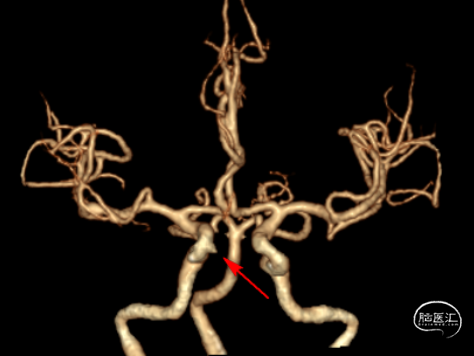

术前CTA:右侧颈内动脉C6段可见一动脉瘤(红色箭头示)。

术前行DSA检查:右侧颈内动脉眼动脉段可见一动脉瘤,瘤体大小4.1*3.2mm,瘤体尾部稍尖,朝向内侧。